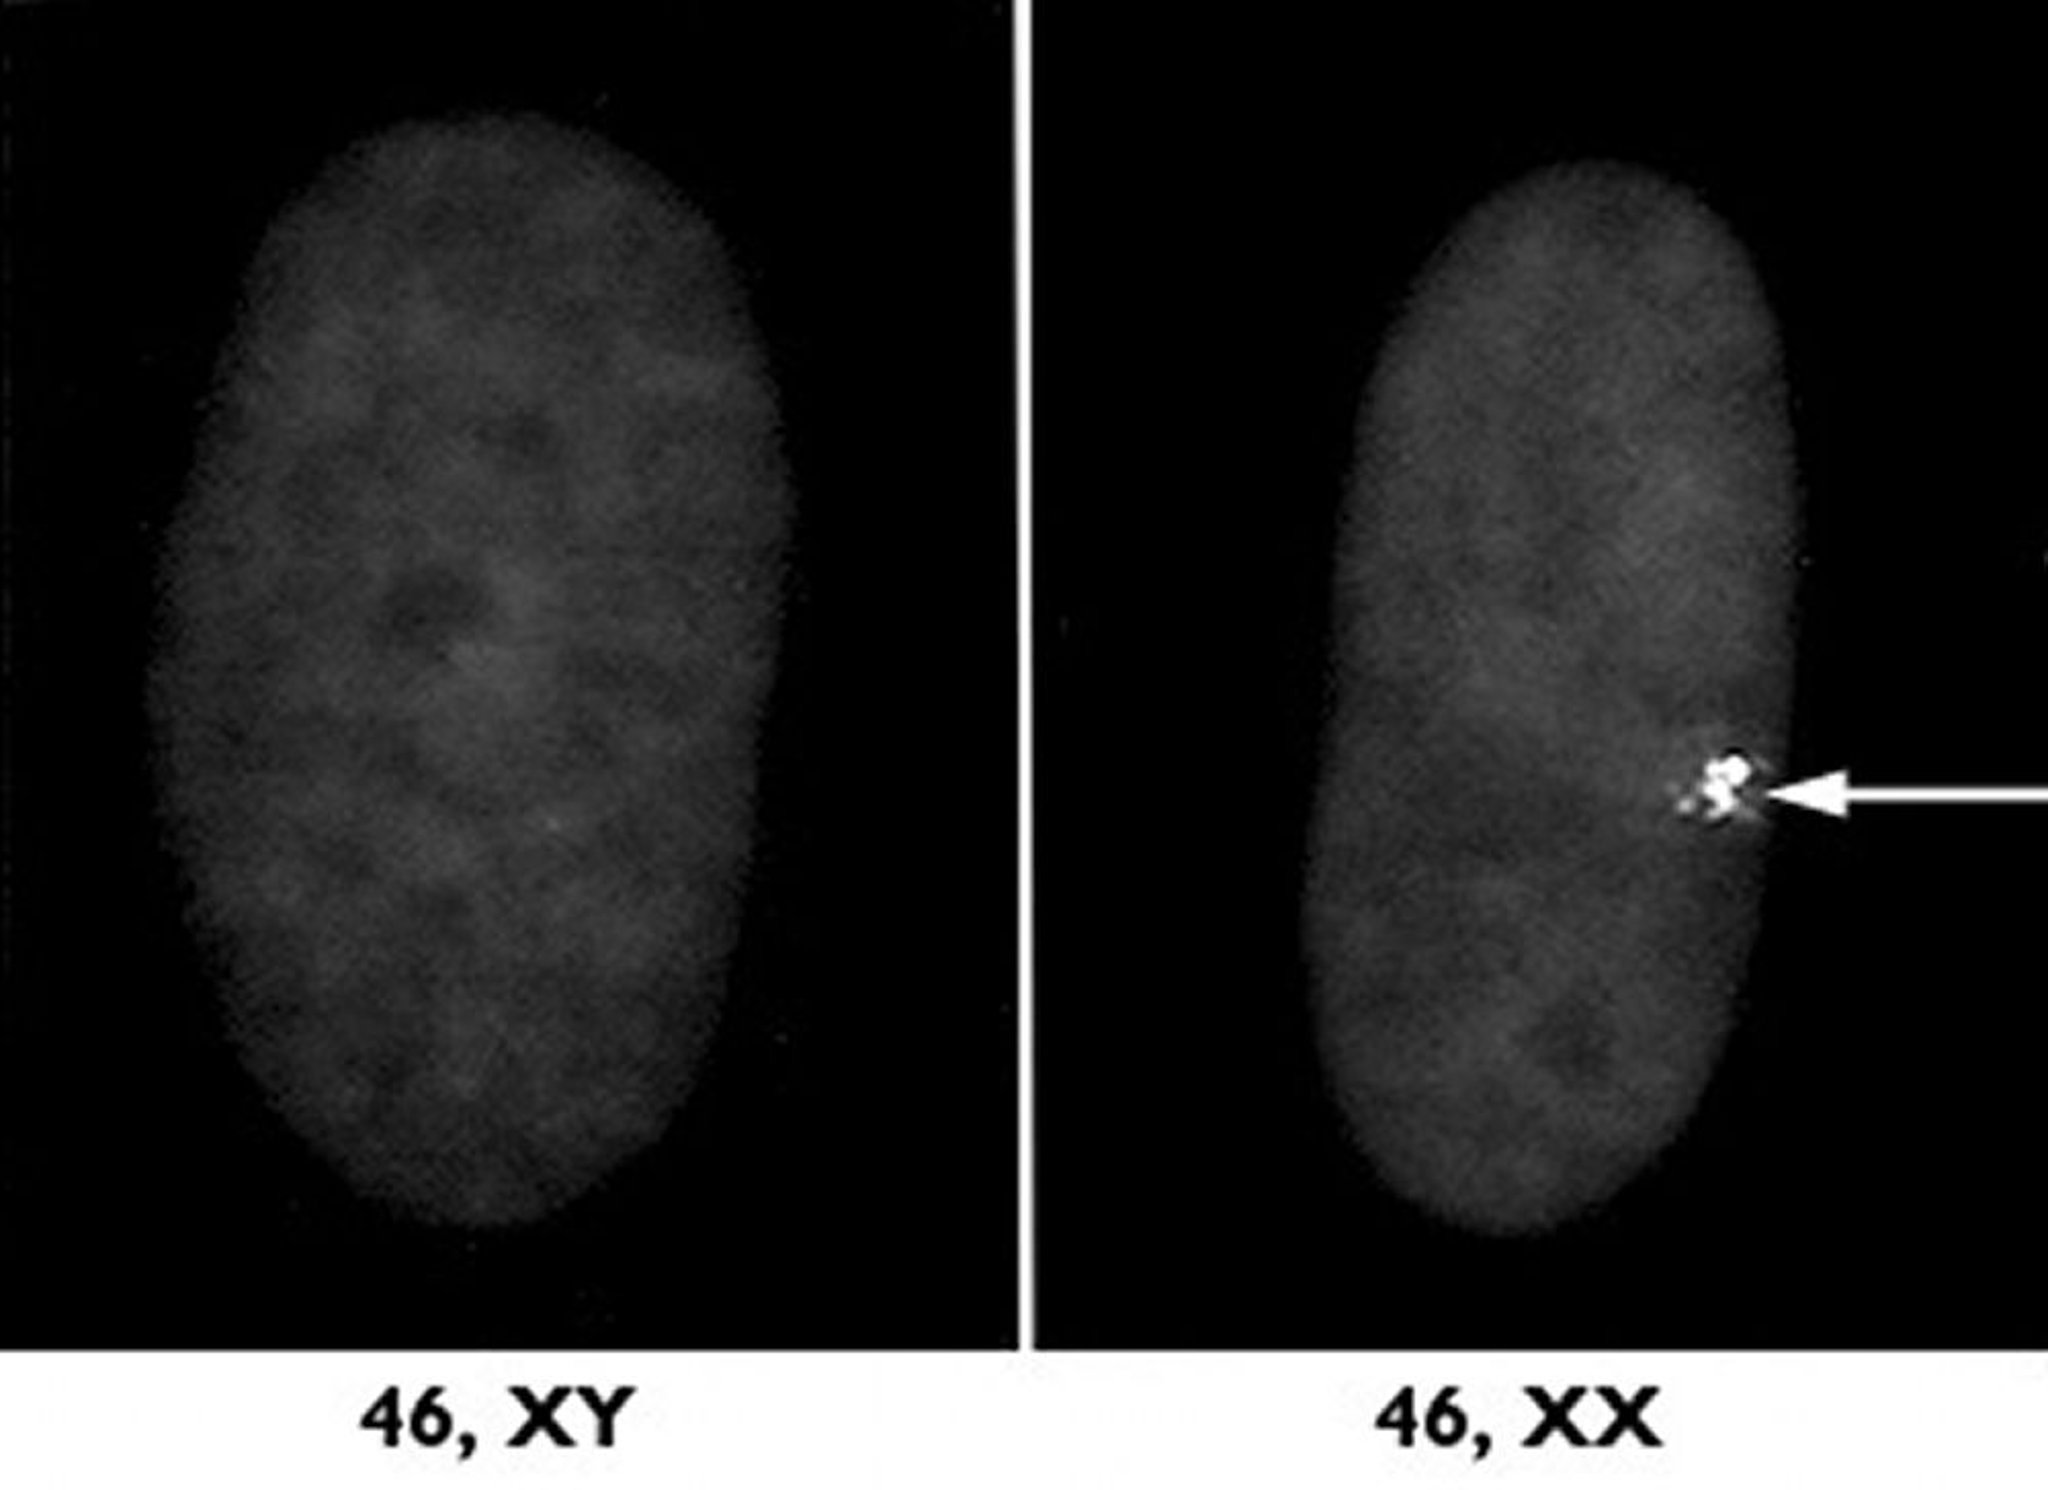

Inaktives X-Chromosom

Eines der zwei X-Chromosomen bei Frauen wird durch den sogenannten X-Inaktivierungsprozess unterdrückt. Rechts zeigt die Probe unter dem Mikroskop einen Zellkern dieses inaktiven weiblichen X-Chromosoms als dichten Klumpen (Pfeil). Links sieht man eine männliche Probe zum Vergleich.

Mit freundlicher Genehmigung von Dres. L. Carrell und H. Williard, Case Western Reserve University School of Medicine.